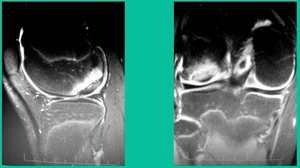

The only other thing to know is about stability. This is probably the most important physiology tenet. This is a biologic problem, because it’s a fracture non-union. But it’s a biomechanical problem because they’ve got a pebble in their shoe when they become symptomatic. So, we talk about the MRIs showing stability. The reality is if they hurt, they probably have microscopic instability. The challenge is if you take a microscopic versus a macroscopically unstable one, the treatment will differ.

Who’s going to heal in the young group? It’s going to be someone who’s much younger. Non-weight-bearing location. Lateral aspect of the medial femoral condyle can often be non-weight-bearing. Smaller lesions, no MRI signs of gross macro-instability, and the absence of sclerosis in cysts. These might heal.

You look at this one, you say, “what are you going to see when you get in there?” This is one when you get in there, you say, I’m not even sure I’m in the right knee because you almost don’t see it. That happens in patients who were painful, but they don’t look macroscopically unstable. Pediatric orthopedic surgeons tend to drill these. These are the ones that I see as failures. I think when you’re talking about something that’s mechanically unstable, it’s hard to understand why drilling would actually make it work without fixation. Even if it’s microscopically unstable.

The challenge is this. This series of patients were populated by early decisions to treat when patients don’t have symptoms. That’s a problem in my mind. Post-Op, they protect their weight-bearing. That’s actually treatment. These are often smaller lesions of the medial femoral condyle. They do really well. That being said, it’s an option. It’s not my option. My option for someone who’s macroscopically unstable is we use biocomposite screws (Figure 4).

Worsening over the last two years, has effusions but no locking, and has a large area of involvement that appears unstable. This is the classic fixation. If you can do this, this is the holy grail. Remember, fracture non-union: you elevate it, debride the base, get rid of any unstable fragments, just take them out, and preserve the major fragment. I’ll use a microfracture awl, but most commonly now I’ll use a pick or a pin, and I’ll drill it. I use two to three metal screws. I bury their heads, and then I come back at eight weeks after being non-weight-bearing, and pull the screws out.